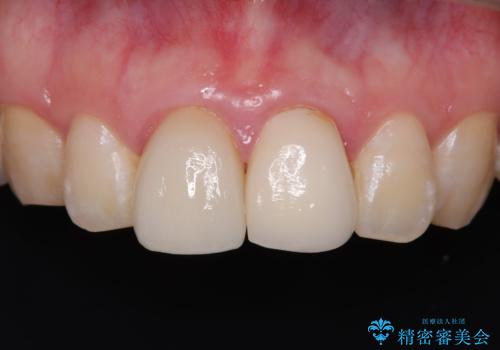

前歯の根のところに違和感がある|根尖性歯周炎|精密根管治療|オールセラミッククラウン|見た目も改善